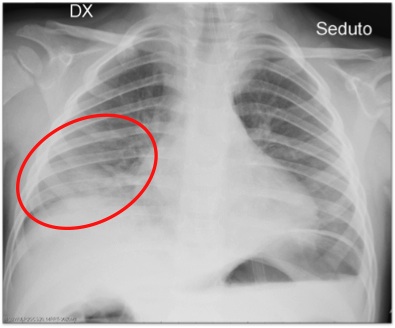

M. (4 anni), mentre era in piscina, � rimasto immerso sott�acqua per circa un minuto finch� la madre non l�ha soccorso. Ha vomitato subito e non ha mai perso coscienza anche se era sonnolento. All�ingresso in Pronto Soccorso si presenta lucido, orientato, dispnoico con SaO2 85% in aria ambiente e all�auscultazione toracica presenta rumori umidi a destra e addome globoso con stomaco dilatato per la presenza di liquido. Si somministra subito ossigeno-terapia e metilprednisolone. Gli esami ematici mostrano un�acidosi (pH 7,28), una modesta ipernatriemia, un�iperglicemia da stress con emocromo e PCR nella norma. L�Rx torace (Figura 1) evidenzia un addensamento alla base destra. Visto l�addensamento polmonare e la storia di inalazione, � stata avviata terapia antibiotica con ceftriaxone e metronidazolo. In seguito le condizioni cliniche sono progressivamente migliorate, � stata prima ridotta e poi tolta la supplementazione di O2, l�emogasanalisi e la sodiemia si sono normalizzate. Prima della dimissione (a 24 ore dall�arrivo in ospedale) gli � stata somministrata un�ulteriore dose di steroide e al domicilio ha proseguito la terapia antibiotica con amoxicillina-acido clavulanico.

Figura 1. Rx del torace che evidenzia un addensamento alla base destra.